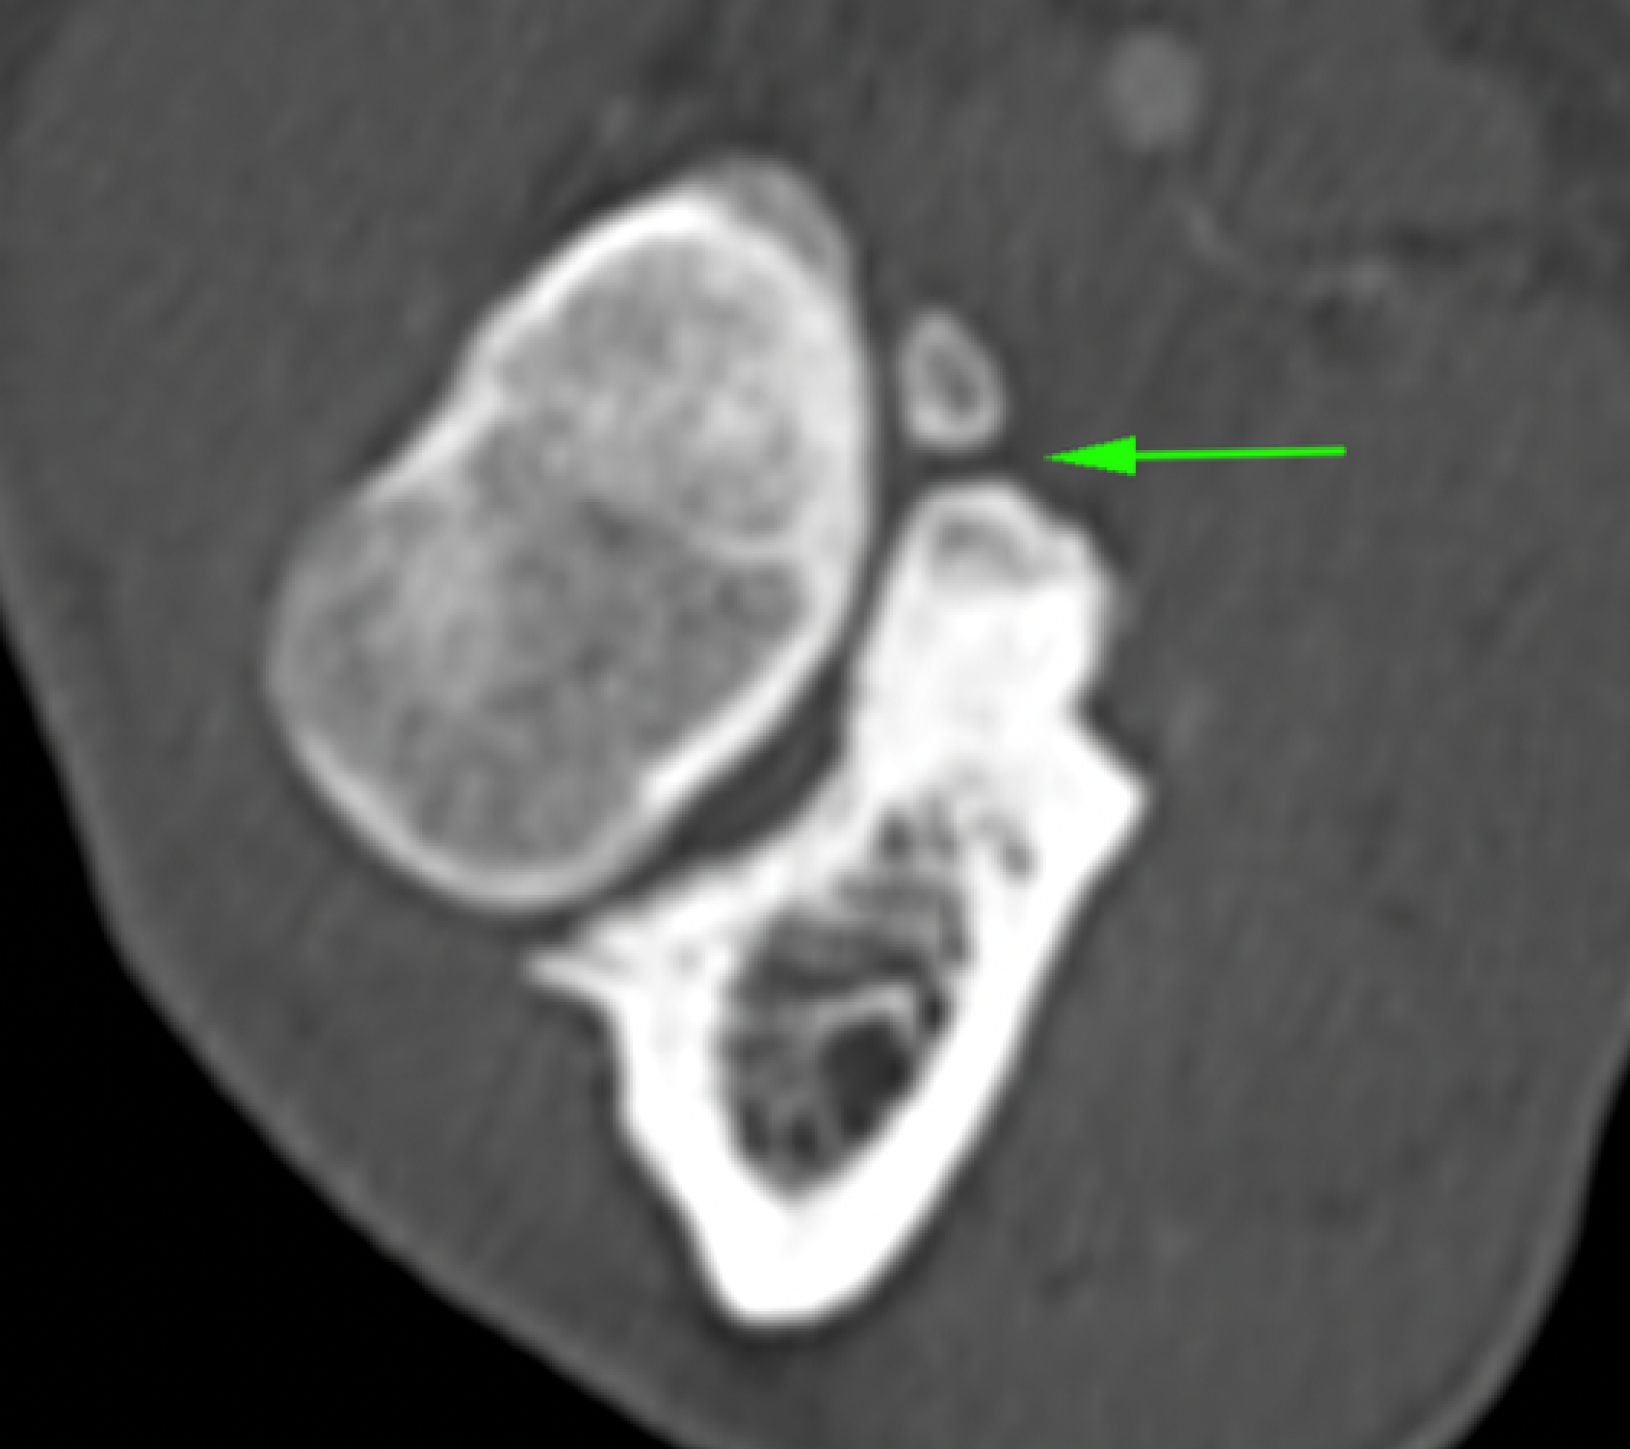

La Tomografía computerizada (CT) o TAC es la técnica por imagen de elección. El procesado avanzado de la imagen nos permitirá visualizar finos cortes de la anatomía y detectar pequeñas lesiones (por ejemplo, fragmentación del proceso coronoides), las cuales son difíciles de diagnosticar en radiografías convencionales.

• Enfermedad del proceso coronoides medial (EPCM): se trata de la condición más encontrada de todas las que se incluyen en la displasia de codo. El proceso coronoides puede encontrarse malformado, fisurado e incluso fragmentado. Como resultado de esta enfermedad y del roce anormal de dicha estructura con la superficie articular del cóndilo humeral medial, se produce un desgaste acelerado de las superficies cartilaginosas del aspecto medial del codo dando lugar al Síndrome del compartimento medial, el cual se ve favorecido por la sobrecarga que soporta la región interna de la articulación en condiciones fisiológicas.

• Incongruencia de codo: hace referencia a una conformación anormal de las superficies articulares, normalmente a consecuencia de un radio o un cúbito más cortos de lo habitual, o bien a una incisura cubital más cerrada o abierta de lo normal.